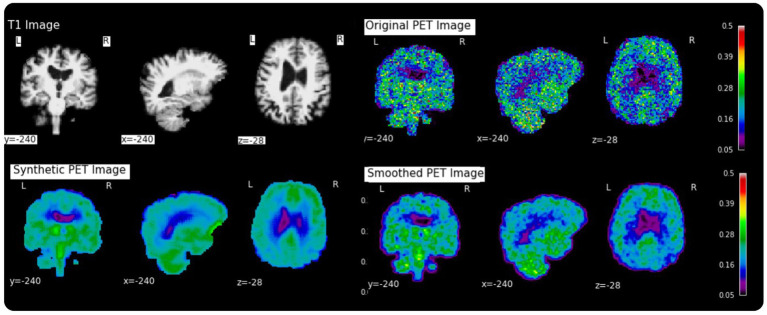

Generation of synthetic TSPO PET maps from structural MRI images.

Results: The model achieved a low voxel-wise mean squared error (0.0033 ± 0.0010) across all folds and a median contrast-to-noise ratio of 0.0640 ± 0.2500 when comparing true to reconstructed PET images. The synthesized PET images accurately replicated the spatial patterns observed in the original PET data. Additionally, the reconstruction accuracy was maintained even after spatial normalization.